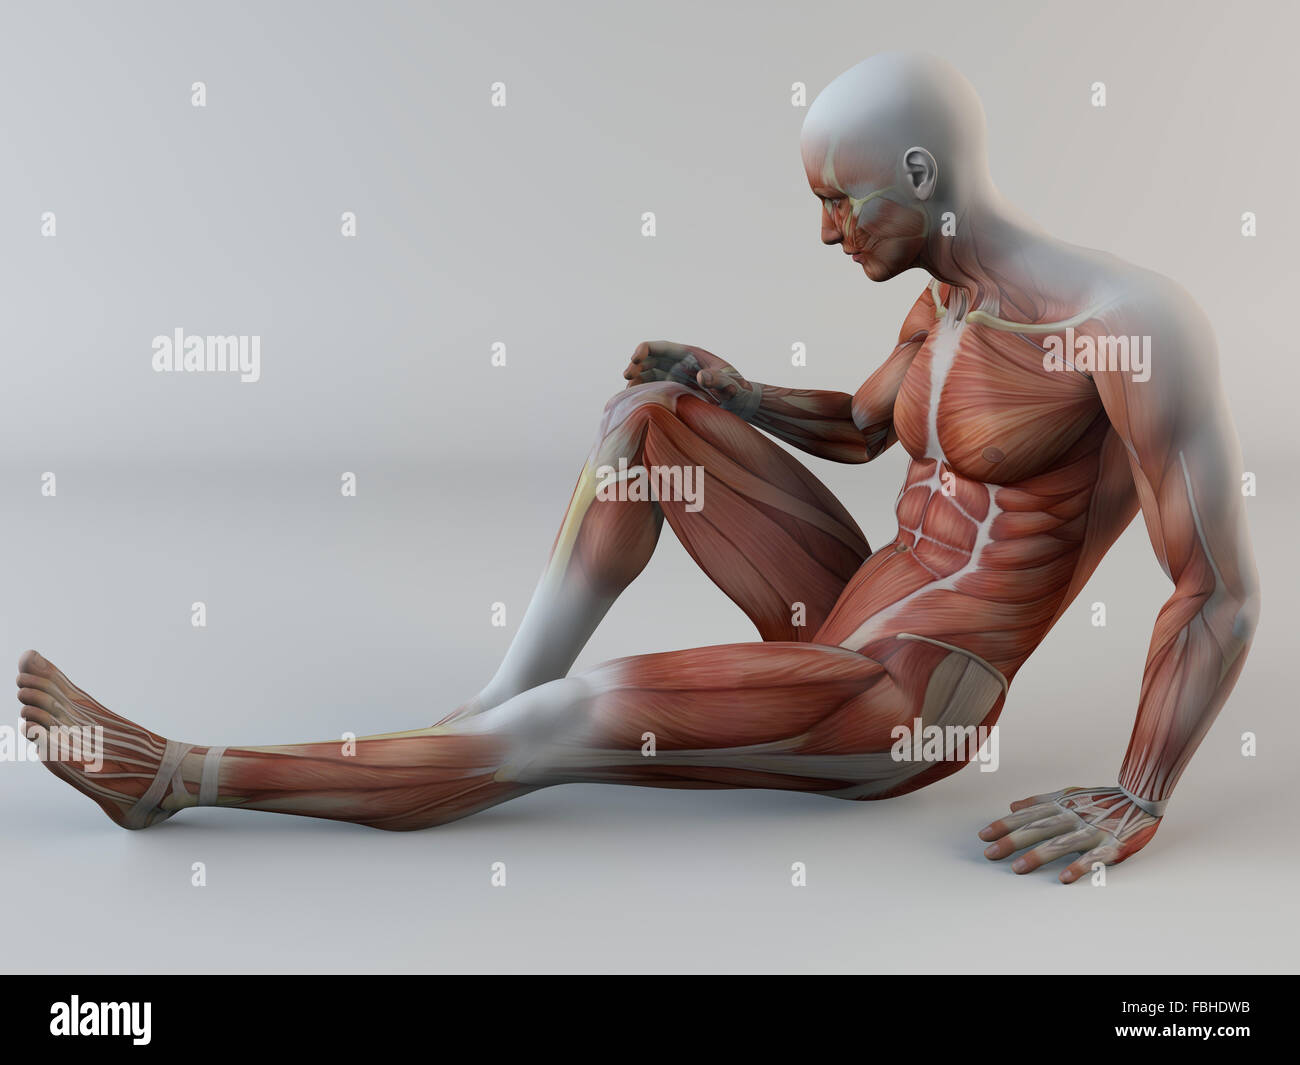

3d, corps humain, douleur au genou, muscles, déchirure musculaire Banque D'Imageshttps://www.alamyimages.fr/image-license-details/?v=1https://www.alamyimages.fr/photo-image-3d-corps-humain-douleur-au-genou-muscles-dechirure-musculaire-93197143.html

3d, corps humain, douleur au genou, muscles, déchirure musculaire Banque D'Imageshttps://www.alamyimages.fr/image-license-details/?v=1https://www.alamyimages.fr/photo-image-3d-corps-humain-douleur-au-genou-muscles-dechirure-musculaire-93197143.htmlRFFBHDWB–3d, corps humain, douleur au genou, muscles, déchirure musculaire